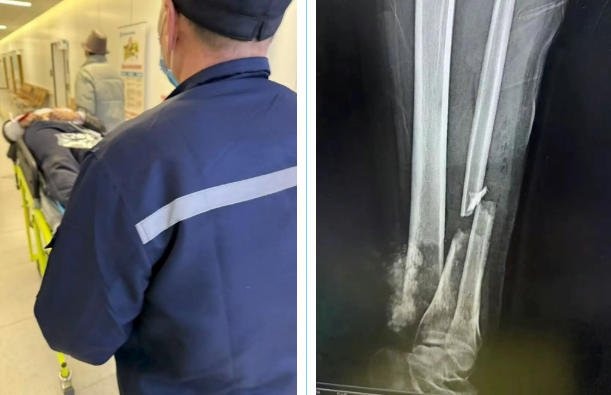

现场情况比预想的更为严峻。伤者22岁,意识尚清,但声音虚弱,手腕肿胀变形,左下肢胫腓骨断裂外露,出血较多。医护团队予以专业包扎和夹板固定后,小心翼翼地将其搬运上救护车。护士迅速建立静脉通路,进行心电监护、给予抗休克药物,监测生命体征。

入院途中,冀晓彬及时上报系统,提前通知急诊科。我院创伤救治绿色通道迅速开启,当救护车到达医院时,接诊团队早已准备就绪。经过紧急检查和急会诊,伤者生命体征暂时平稳,收治骨科进一步开展手术。至此,一场紧急的救护接力赛顺利结束。